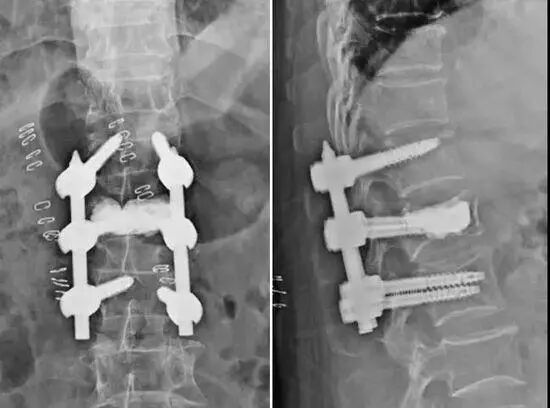

病例:患者李某,83歲,因不慎從樓梯摔落導(dǎo)致腰背部劇烈疼痛,活動(dòng)時(shí)加重,站立及行走困難,診斷為:腰1椎體爆裂性骨折、腰椎椎管狹窄。

目前,脊柱外科已開展微創(chuàng)經(jīng)皮釘棒內(nèi)固定術(shù)治療脊柱骨折多年,技術(shù)成熟,手術(shù)時(shí)間短,安全性高,效果滿意。該患者合并嚴(yán)重骨質(zhì)疏松,單獨(dú)釘棒內(nèi)固定易導(dǎo)致內(nèi)固定松動(dòng)、斷裂。經(jīng)科室反復(fù)討論及與患者及其家屬商議后,決定為患者行微創(chuàng)經(jīng)皮釘棒內(nèi)固定術(shù)+微創(chuàng)經(jīng)皮椎體成形術(shù)!兩種微創(chuàng)術(shù)式相結(jié)合,不僅可以很好地恢復(fù)椎體高度,穩(wěn)定骨折,還能讓患者早期下地活動(dòng),減少臥床相關(guān)并發(fā)癥,遠(yuǎn)期效果更佳。

耗時(shí)約2小時(shí),手術(shù)順利完成。術(shù)后第一天,患者即可佩戴支具坐起,自主完成進(jìn)食等動(dòng)作;術(shù)后第二天,原腰部疼痛大部分緩解,可佩戴支具在陪人幫助下下地活動(dòng);術(shù)后第五天,患者佩戴支具在扶手架輔助下在病房走廊行走;術(shù)后十天,患者順利拆線出院;術(shù)后一月余,醫(yī)生電話隨訪,患者可自行穿戴支具并自行下地活動(dòng),恢復(fù)生活自理能力。